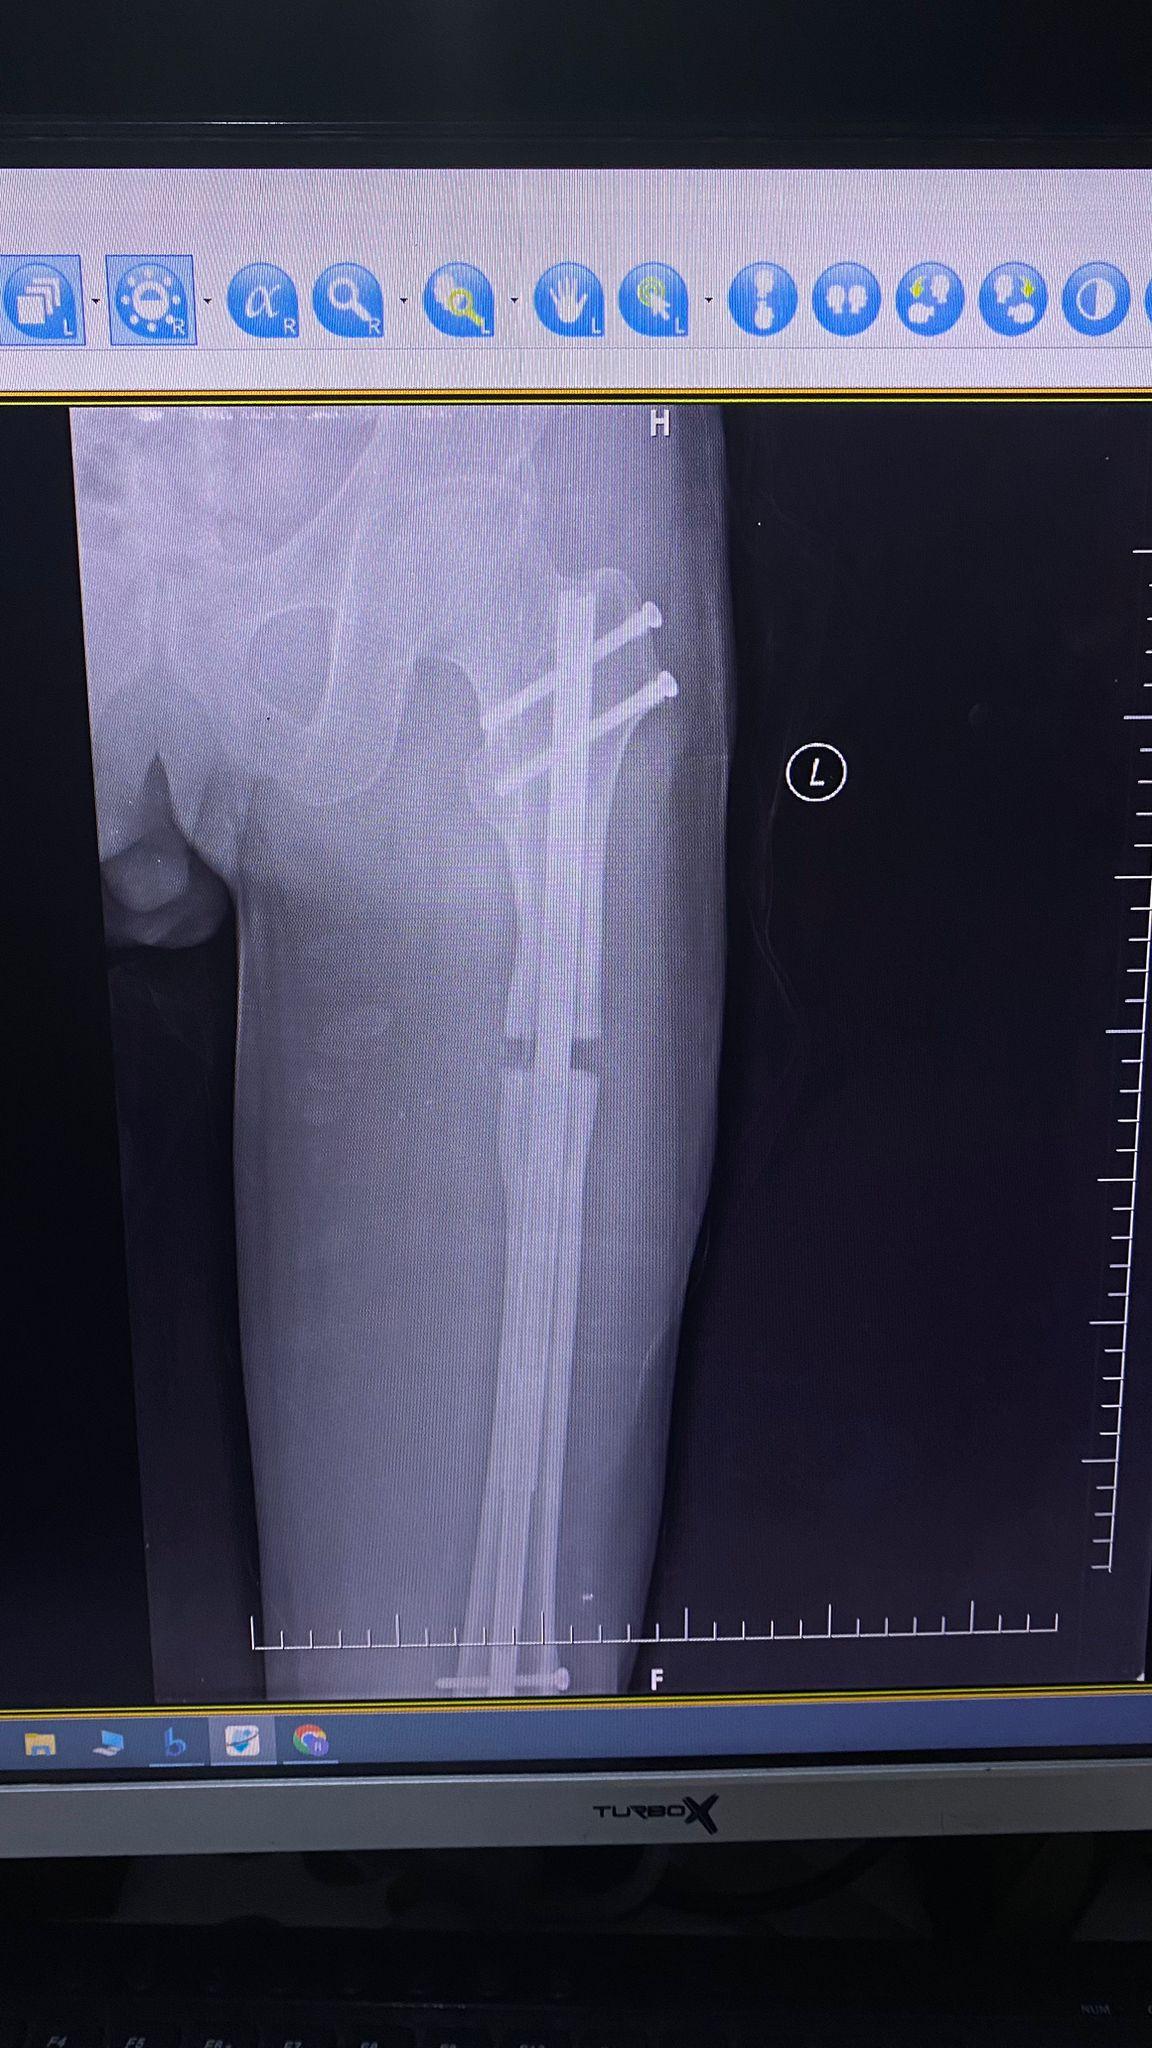

Precice 2 uzuv uzatma sistemi, ABD merkezli tıbbi cihaz üreticisi NuVasive tarafından geliştirilmiş yüksek teknoloji bir içten uzatma yöntemidir. Bu sistem, kemiğin içine yerleştirilen biyouyumlu bir çivi ve dışarıdan kullanılan ERC (External Remote Controller) sayesinde kemiğin kontrollü ve hassas bir şekilde uzatılmasını sağlar.

Precice 2, kemiğin içine yerleştirilen titanyum bir çivinin manyetik güçle kontrollü şekilde uzatılması prensibiyle çalışır. Hastalar, günde üç kez ERC cihazı ile her seferinde 0,33 mm olmak üzere kemik uzatması gerçekleştirir.

Tibia ve Femurda Yüksek Uzama Kapasitesi

• Tibia: 6 cm

• Femur: 8 cm’ye kadar güvenli uzama sağlar.